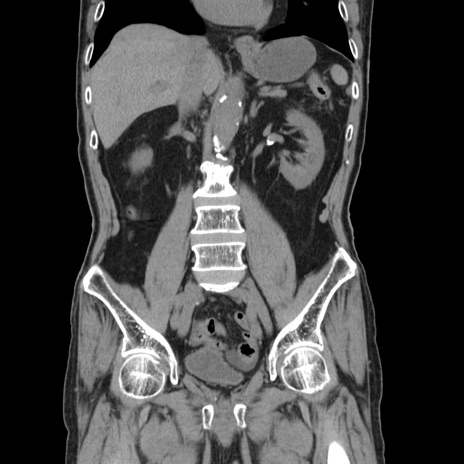

症例24(冠状断像)

【症例】80歳代男性

【主訴】左側腹部痛、嘔吐

【現病歴】本日早朝より左腹部に痛みあり。昼頃嘔吐認めたため、救急要請。

【既往歴】直腸癌(Mile手術)、胆摘

【身体所見】意識清明、BT 35.9℃、BP 221/93mmHg、SpO2 97%(RA) 、腹部:左ストーマ周囲に限局性の腹部膨隆あり。 膨隆部自発痛・圧痛あり・軟。

【データ】WBC 7700、CRP 0.09